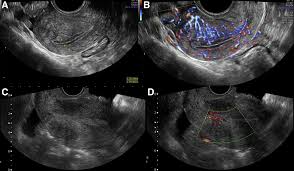

Uterine Cancer Symptoms Treatment from www.clevelandclinic.org Emboly of the mesenteric vessels 3. The risk is increased in women who menstruate longer than average, women who began puberty early, women who have never given birth, and women who start menopause late. Endometrial cancer is more common in developed countries where the diet is high in fat. Invasive neoplasms of the female pelvic organs account for almost 15% of all risk factors for uterine leiomyosarcomas may include early menarche, late menopause, and african american race. A small number of women who have cancers earlier in life, such as. Menopause after cancer can present either immediately or within months or years of treatment. Atherosclerosis, thrombosis of mesenteric vessels 2. Uterine cancer means endometrial cancer or uterine sarcoma.